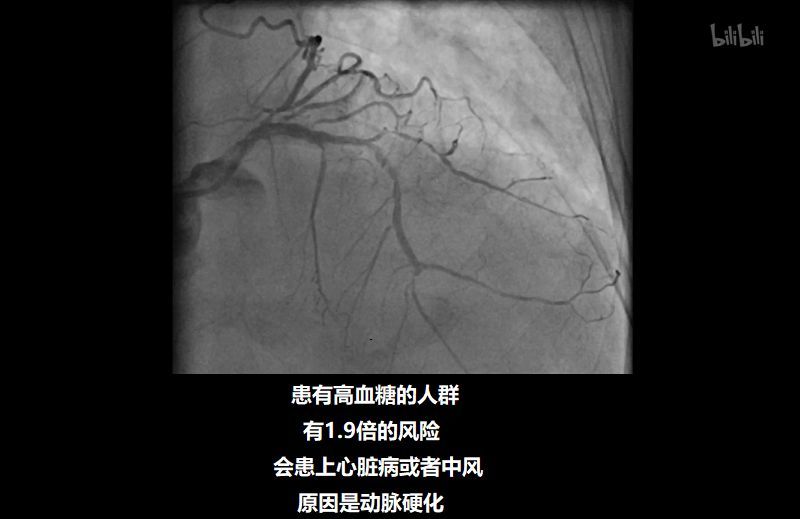

研究显示,患有高血糖的人群,患上心脏病或中风的风险是正常人的 1.9 倍。

这时,动脉壁的免疫细胞会吸收它们,把它们粘附在动脉壁上,造成 动脉壁膨胀,血管变窄,较终导致动脉硬化。

左边是正常人的动脉影像

右边是高血糖患者的动脉影像,血管壁很细